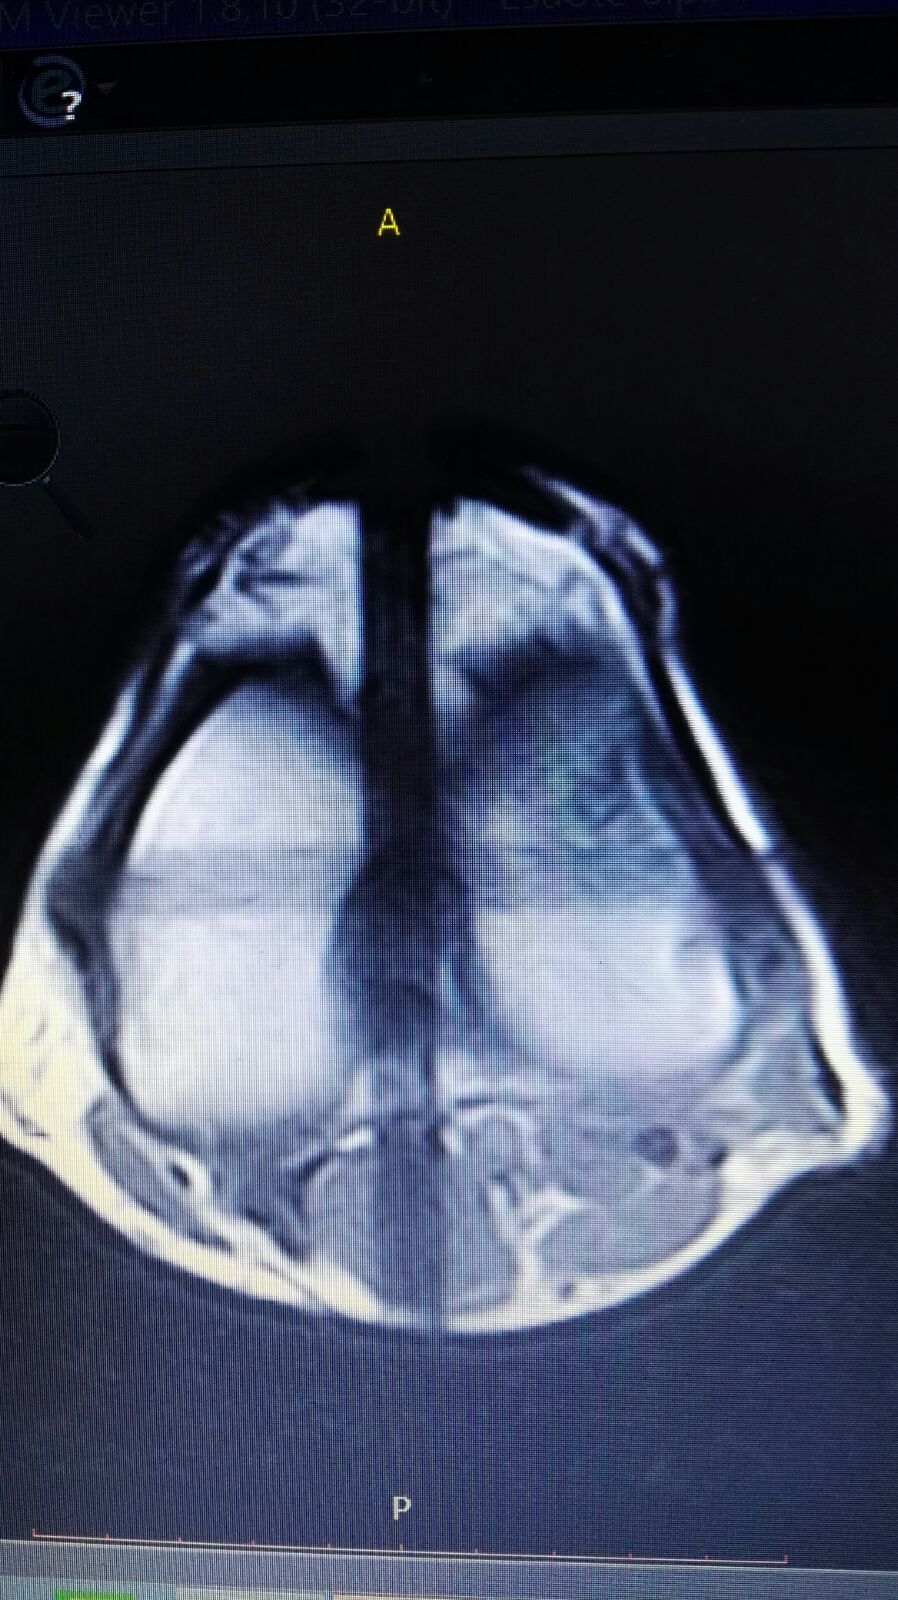

Le ho inviato qualche altra foto

IMG-20180301-WA0017.jpg

[ 239.83 KiB | Osservato 1320 volte ]